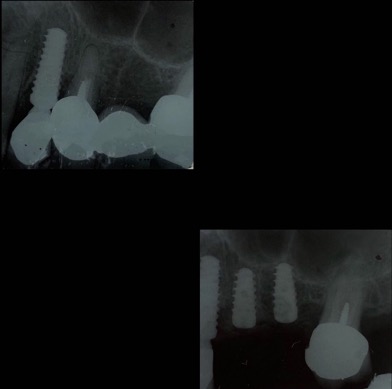

Un impianto dentale o fixture è un corpo in titanio, totalmente biocompatibile, che viene posizionato nella mascella o mandibola con lo scopo di sostituire la radice di un dente naturale perso. Su di esso viene successivamente o immediatamente quando possibile (carico immediato) fissata la protesi ovvero la corona del dente restituendo funzione ed estetica.

Nulla è per sempre, come anche i denti naturali. Un impianto può andar incontro ad una perimplantite, infiammazione che attacca il tessuto osseo circostante fino a causarne la mobilità. I fattori che predispongono alla perdita di un impianto sono: fumo di sigaretta, scarsa igiene orale, sovraccarico meccanico, predisposizione genetica. Le cause certe non sono ancora del tutto note al giorno d’oggi.

Qualità degli impianti e tipo di trattamento di superficie, caratteristiche nel design della protesi e corretto posizionamento sono fattori fondamentali per ridurre il rischio di perdere un impianto.